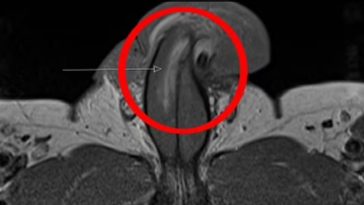

Όπως ανέφερε, κατά τη διάρκεια της πράξης, “κάτι δεν πήγε καλά” και το πέος του έδειχνε να έχει υποστεί ρήξη.

- Οι γιατροί του νοσοκομείου πραγματοποίησαν λεπτή χειρουργική επέμβαση για να αποκαταστήσουν τη ζημιά. Παρόλο που η επέμβαση φαίνεται να ήταν επιτυχής, ο ασθενής αντιμετώπισε σημαντική ψυχολογική δυσφορία από το συμβάν, με πιθανή ανάγκη για ψυχολογική υποστήριξη.